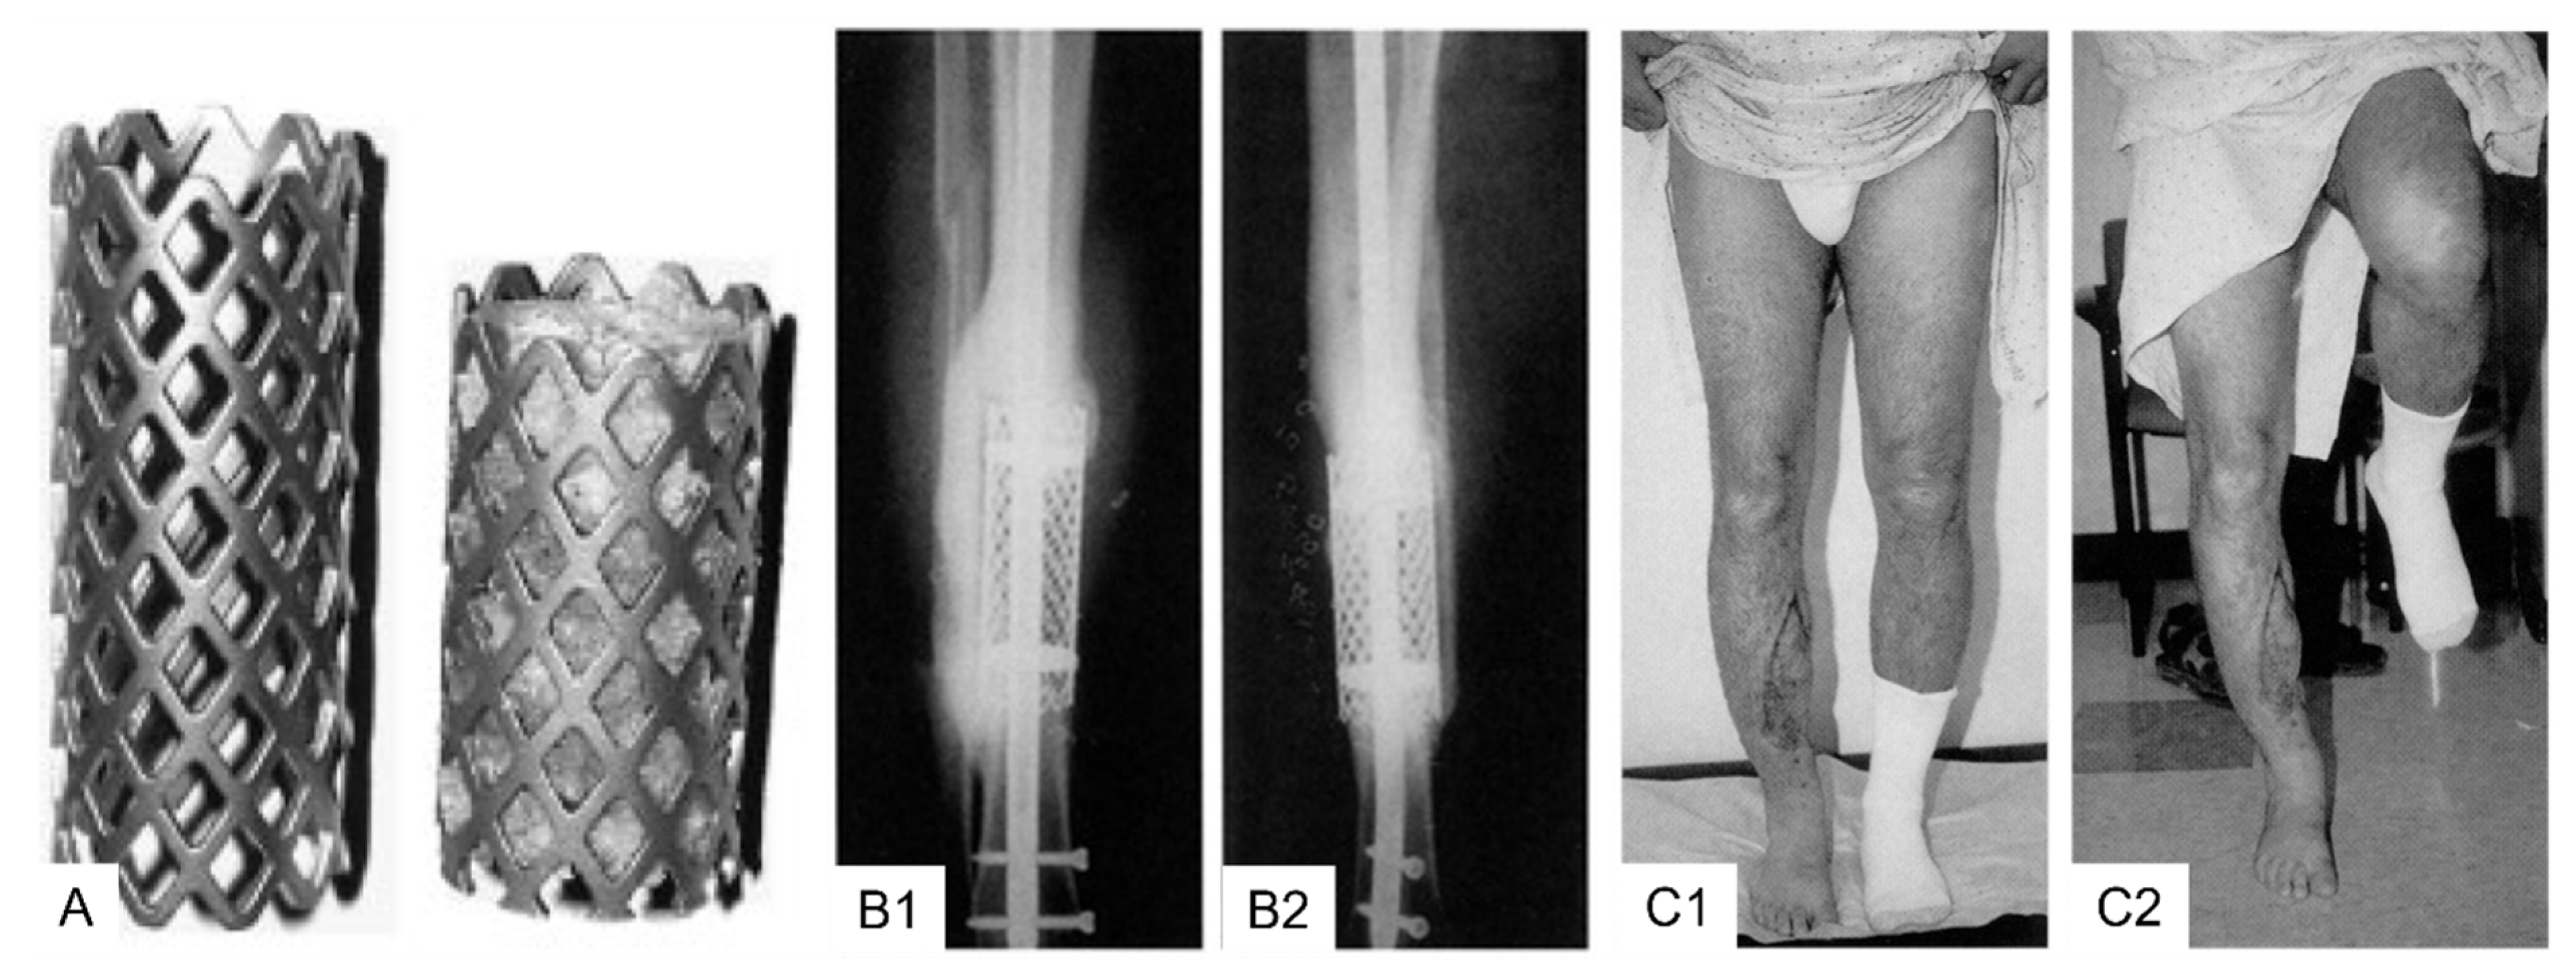

3.2. Clinical Application Cylindrical (Spinal) Titanium Mesh Cages for Long Bone Defects